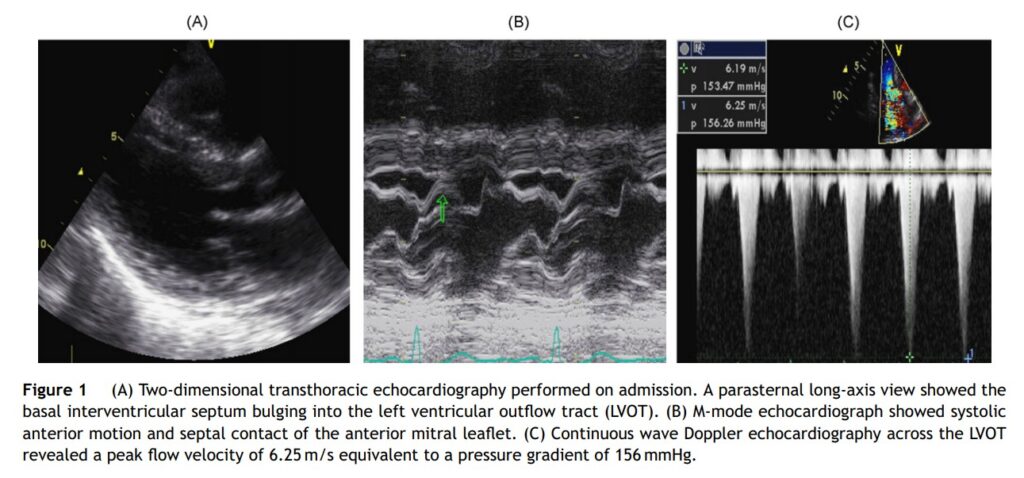

Mulher, 71 anos de idade, sem histórico de eventos cardiovasculares prévios, admitida por queixa de dispneia aos esforços. Apresentava-se com pressão arterial de 200×100 mmHg e radiografia de tórax demonstrada congestão pulmonar moderada a severa.

Exames laboratoriais evidenciavam anemia macrocítica com hemoglobina de 7.4 g/dL e hematócrito de 26%, cuja etiologia foi posteriormente atribuída ao diagnóstico de úlcera péptica.

Cateterismo cardíaco não documentou doença coronária obstrutiva, porém mostrava gradiente de 80 mmHg na via de saída do ventrículo esquerdo.

Ecocardiograma mostrou hipertrofia focal da região basal do septo interventricular, presença de SAM, com velocidade de pico na via de saída de 6.25 m/s e gradiente máximo de 156 mmHg.

Após realização de transfusão sanguínea (hemoglobina 12.4 g/dL), foi observada redução significativa do gradiente pressórico na via de saída do ventrículo esquerdo (14 mmHg) e ausência de SAM, bem como melhora dos sintomas relatados pela paciente.

Assim, ficou documentada obstrução dinâmica da VSVE induzida pela anemia.